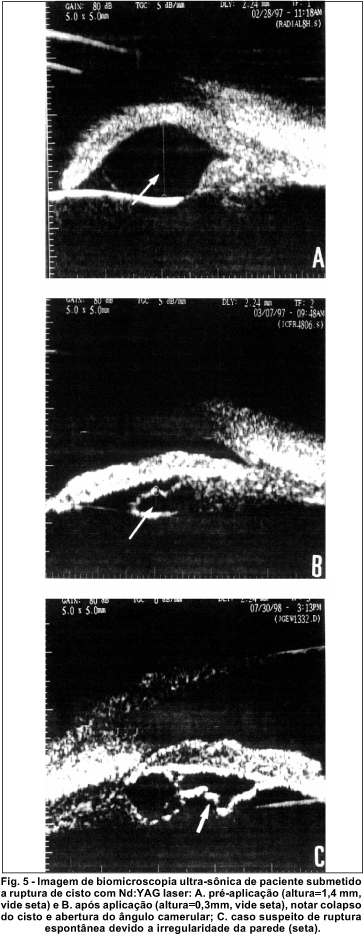

Na série deste estudo pôde-se observar um paciente referido com diagnóstico de glaucoma e síndrome de íris em plateau. O UBM revelou bilateralmente câmara anterior rasa, com fechamento angular por 360o e múltiplos cistos irianos em olho direito, localizados nos meridianos de 8, 9 e 10, e, em olho esquerdo, nos meridianos de 3, 4, 5 e 6; a íris apresentava-se retificada e o corpo ciliar anteriorizado. Notou-se também iridectomia a laser em ambos olhos, procedimento realizado previamente para controle da pressão intra-ocular. Em nosso estudo pôde-se observar as imagens ecográficas de um paciente portador de múltiplos cistos em íris e corpo ciliar, acometendo os meridianos de 3, 4, 7, e 8, sendo que este último apresentava fechamento angular. O paciente foi submetido à ruptura do cisto de maior dimensão (altura=1,4 mm) com Nd:YAG laser e conseqüente colapso da cavidade cística e enrrugamento da parede (altura após aplicação = 0,394mm), com abertura do ângulo camerular (figura 5).

Dentre os pacientes examinados, um apresentou formações císticas, múltiplas, bilaterais, e o cisto de maior volume apresentava parede irregular, supostamente colapsada, com suspeita de ruptura espontânea do cisto, já que não havia história pregressa de intervenção cirúrgica (figura 5c).

Estes cistos raramente requerem tratamento. Em casos de procedimentos como o uso de Nd:YAG laser, as imagens obtidas pela UBM no pré-operatório e após a sua aplicação revelaram a eficácia do tratamento, mostrando o colapso do cisto após sua ruptura.